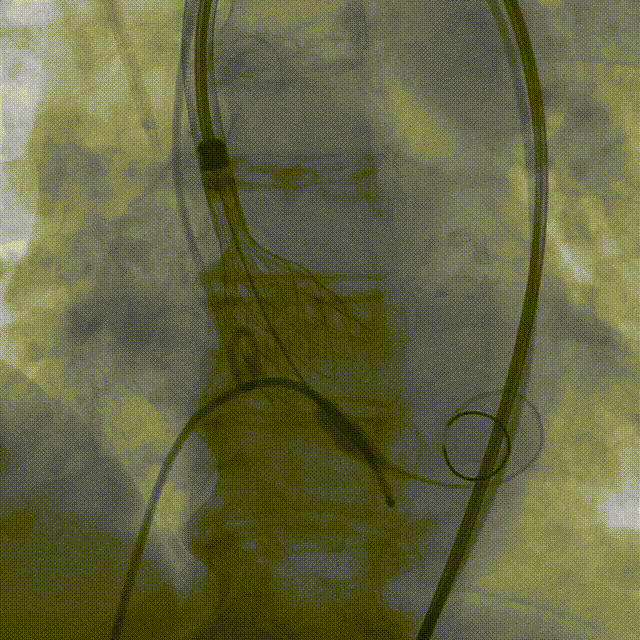

TaurusNXT植入过程

术中影像

主动脉根部造影

TaurusAtlas 18mm球囊预扩张

瓣膜释放至工作位造影

最终造影